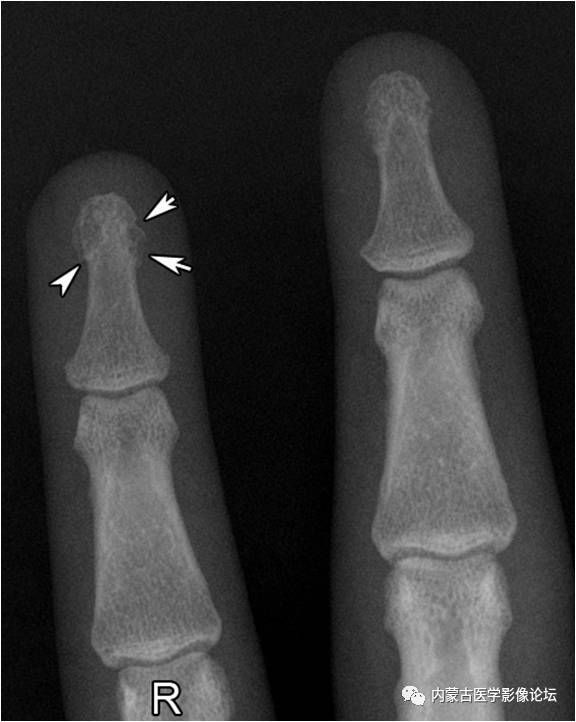

指骨骨皮质增厚:近、中节指骨骨皮质厚而致密,骨髓腔变窄,无病理学意义。

正常指骨粗隆:环指远节指骨粗隆呈不规则分叶状(白箭),部分呈透亮线改变(箭头),但边缘清晰,轮廓线连续,不应误为骨折线或病理改变。